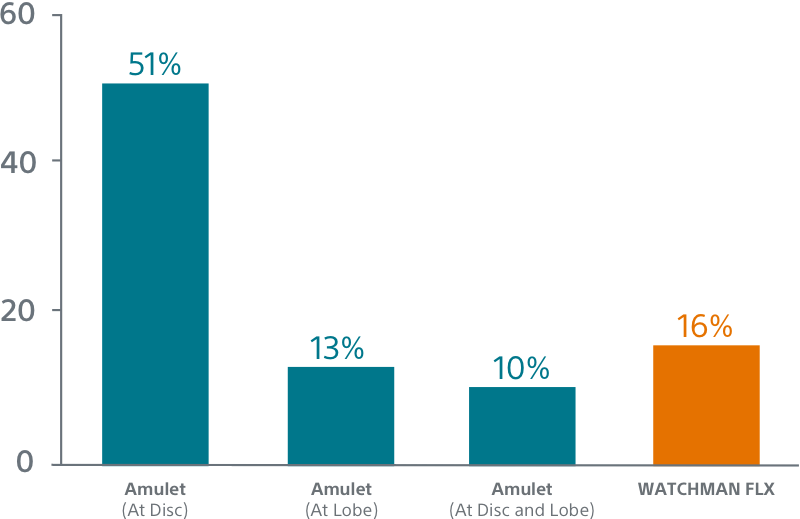

WATCHMAN FLX Demonstrated Statistically Superior Complete Occlusion** vs Amulet (p=0.001)

**Complete LAA occlusion defined as no visible peri-device leak (PDL) and absence of contrast patency in the distal LAA (LAA/left atrium Hounsfield ratio <0.25)

Simplified Assessment

AMPLATZER AMULET1

Hidden Leaks